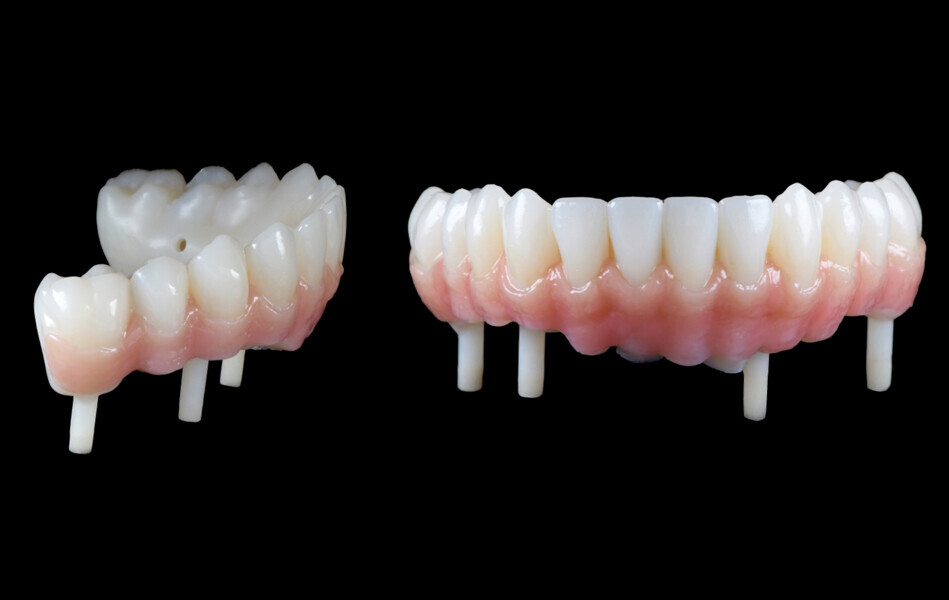

Le projet prothétique (validé préalablement en bouche) peut être aussi numérisé en fichier STP et, dès lors, il peut être combiné avec le fichier STL de la situation initiale. Cela permet de faire apparaître le projet prothétique sur les données osseuses : la planification est alors plus fonctionnelle et biologique. Dans le même temps, il est possible de transformer ce projet prothétique en prothèse provisoire (logiciel DTX Lab) adapté à la planification (perforation de la prothèse en regard de la position des futurs implants et piliers). Cette prothèse comporte également quatre tiges au niveau de l’intrados, dessinées en regard de zones osseuses. Après forage guidé par la navigation, elles permettent de positionner la prothèse correctement (Fig. 7). La prothèse provisoire a été préparée en PMMA et réalisée avec une résine composite rose pour simuler la gencive (Fig. 8).

Il est décidé d’utiliser des implants N1 (Nobel Biocare ; Fig. 10). Les piliers prothétiques sont mis en place et vissés au couple de serrage préconisé, et les piliers provisoires en titane ont été vissés sur les piliers prothétiques (Fig. 11).